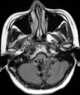

Tumor at fourth ventricle

An ependymoma is a tumor that arises from the ependyma, a tissue of the central nervous system. Usually, in pediatric cases the location is intracranial, while in adults it is spinal. [Source: Wikipedia ]